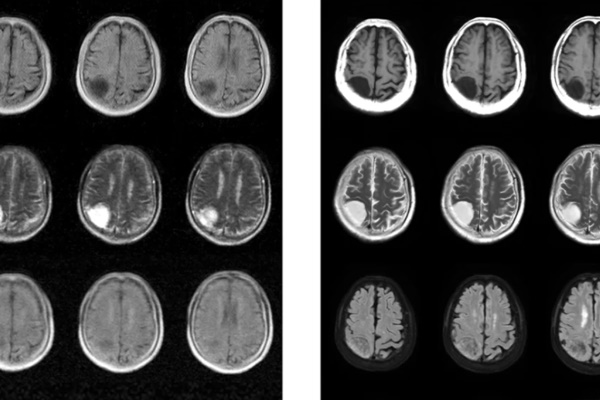

연구팀은 뇌종양 환자 13명, 허혈성 뇌졸중 환자 8명, 출혈성 뇌혈관 질환 환자 4명 등 총 25명을 대상으로 이 장비를 시험했다. 그 이미지들은 3T 자기장을 가진 MRI로 스캔된 이미지들만큼 또렷지는 않았다. 하지만 여전히 대부분의 주요 병증들이 모든 환자들에게서 포착됐다.